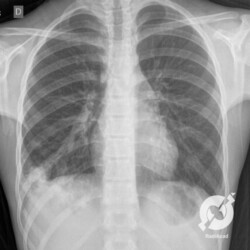

Os agentes etiológicos infecciosos são variados (bactérias, vírus, fungos, parasitas…), mas o que ocorre nos pulmões durante uma infecção por qualquer tipo de agente é a substituição do ar alveolar por secreção (pus, muco, eventualmente sangue ou necrose…) e com isso a manifestação radiográfica vai ser a mesma já que todas estas secreções apresentam a mesma densidade radiográfica: partes moles.

E o nome dado a esta alteração radiográfica que corresponde à substituição do ar alveolar por líquido é a consolidação alveolar.

Uma consolidação alveolar é, por definição, uma opacidade (imagem densa, branquinha) homogênea ou às vezes heterogênea (pela presença de calcificações ou cavidades), de limites mal definidos, exceto quando toca a pleura da parede ou das cissuras pulmonares. É um termo usado tanto em radiografia, como em tomografia computadorizada. Na tomografia, um outro termo é usado: vidro fosco, que é uma opacidade (branquinha mas não tanto como a consolidação), que borra o pulmão mas deixa ver os vasos de permeio (igual bigode de adolescente: dá pra ver todo o fundo).

Nós vamos mostrar aqui um pequeno apanhado de pneumonias de variados agentes, em diversos segmentos e lobos pulmonares, com extensões variadas. O objetivo é identificar o padrão radiológico de consolidação alveolar e não determinar o agente infeccioso, isso vai ser assunto para mais adiante. Aliás já antecipo que é fundamental saber localizar a lesão, porque alguns destes bichos gostam de determinados segmentos, alguns tumores também têm as suas preferências, então localização é fundamental. Se localização não fosse importante, um apartamento na beira do mar sairia o mesmo preço de um apartamento de frente pra BR-101, concordam?